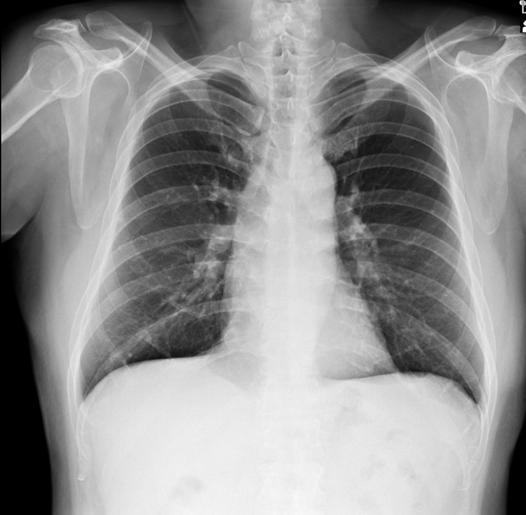

This 54-year-old businessman who had been experiencing intermittent chest pain for the past 6 months.The CCS score was II . He owns 6 factories,lives in high-stress life, combined with a smoking history of 0.5 pack per day for 10 years.Physical examination reveals chronically ill but shows neither abnormal heart sounds nor arrhythmias.Well perfusion of limbs and no pitting edema.Normal chest x-ray.EKG showed normal sinus rhythm without obvious ST changes